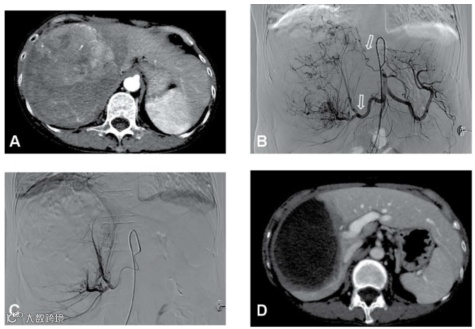

图3.该例大于15 cm的巨大肝癌,经过2次DEB-TACE联合FOLFOX HAIC治疗,肿瘤明显缩小和肿瘤完全坏死